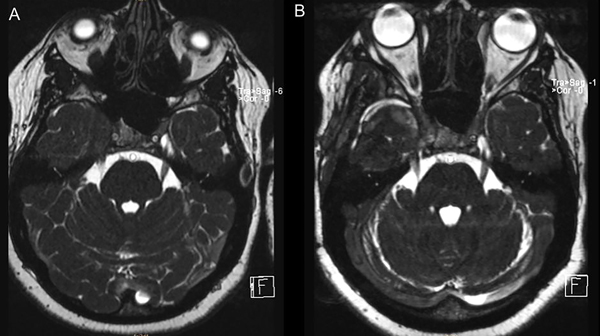

La anatomía patológica informó lesión compatible con pseudotumor inflamatorio. Realizó un mes de tratamiento con corticoides. Se realizó RMN de control a los 2 meses en la que se evidenció importante reducción del volumen de la lesión (Figura 2 y 3).

Figura 2. RMN de cerebro en secuencia T1 con contraste; cortes axial y coronal (A y B). Control a los 2 meses posterior a la cirugía y corticoterapia.

Figura 3. RMN secuencia CISS preoperatoria (A) y control a los 2 meses (B).